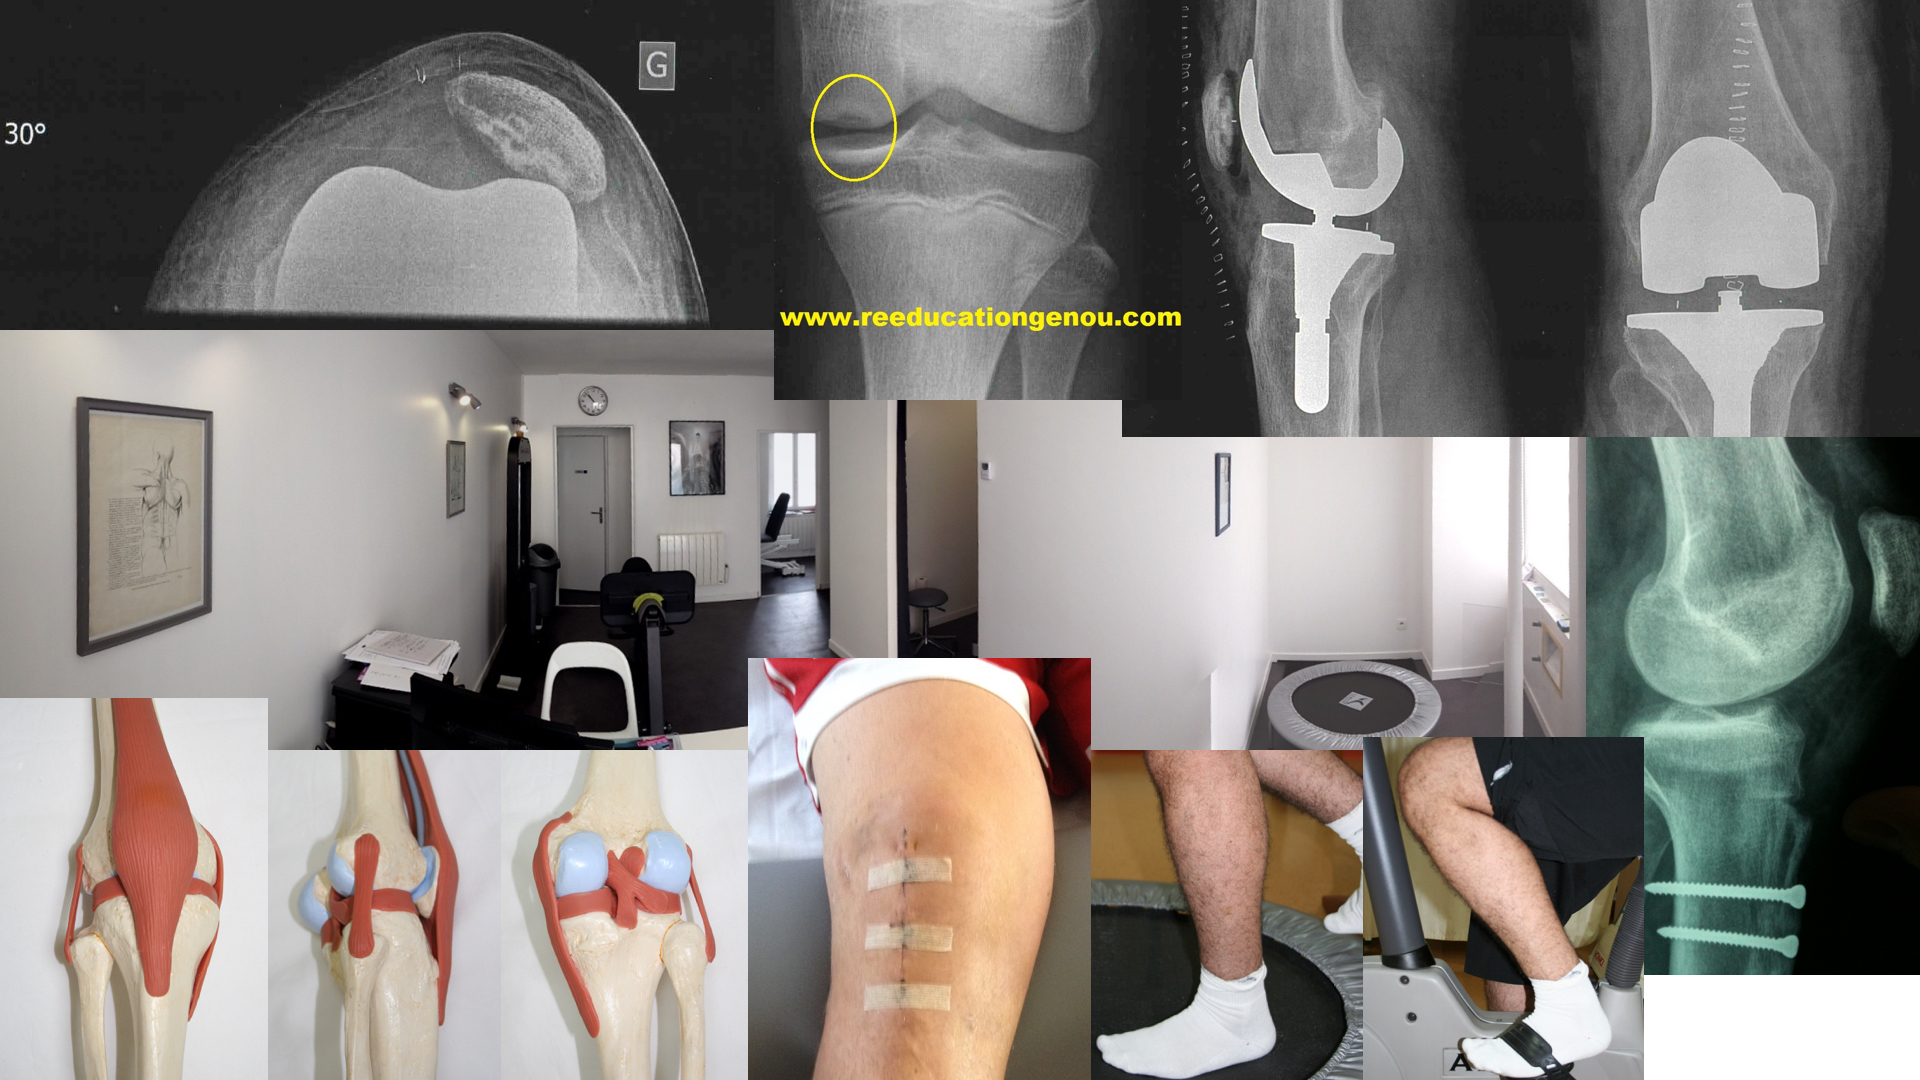

Les ligamentoplasties lors du séjour à la clinique ou hospitalisation

chirurgicalement :

la chirurgie est effectuée